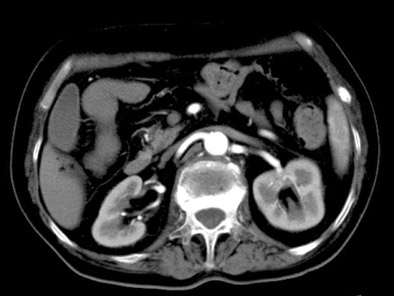

Одним из наиболее информативных диагностических методов при урологических заболеваниях является КТ почек с контрастированием. Исследование, как правило, назначают в тех случаях, когда другие инструментальные методы (УЗИ, рентген) не позволяют уверено установить причины заболевания, степень поражения тканей и другие важные подробности. Современная компьютерная томография позволяет создавать на основе данных, поступающих от датчиков томографа, трехмерную модель почек пациента со всеми присущими этим органам патологиями и индивидуальными особенностями строения. На ее основании рентгенолог формирует заключение о наличии объективных признаков заболевания, которое позволяет урологу или нефрологу разработать эффективную схему лечения.

Изображение в 3D

Пространственное и временное разрешение сделало возможным быстрое построение 3D модели почек. Это обеспечивает высокую диагностическую ценность исследования.

Высокая информативность

3D изображение дополняет спектральная визуализация для определения состава тканей. КТ-диагностика дает полную картину состояния почек при наличии новообразований или конкрементов.

Стол снова задвигается в тоннель, начинается сканирование с контрастным веществом. Датчики, вращающиеся вокруг человека по спирали, снимают сигналы и передают их на компьютер, который формирует 3D изображение почек пациента.